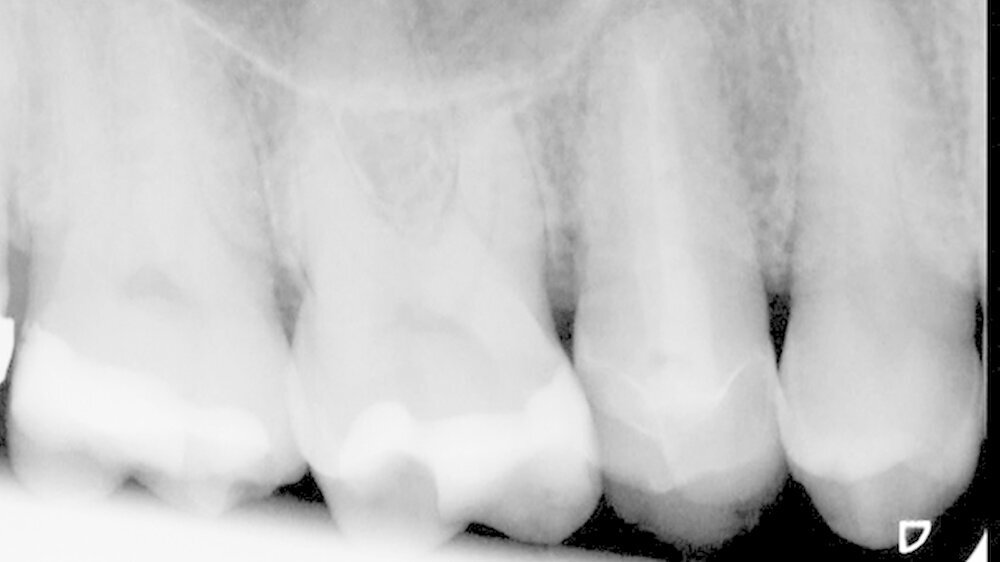

Der Zahn wird replantiert

Die retrograde Präparation und der Frakturspalt wurden mit Biodentine aufgefüllt (Abbildung 7). Während des initialen Aushärtens des Zements wurde die restliche Wurzeloberfläche kontinuierlich mit der Nährlösung der Zahnrettungsbox versorgt. Nach etwa 15 Minuten Aushärtungszeit konnte der Zahn replantiert und im Anschluss für zehn Tage mit einer TTS-Schiene (TTS; Medartis, Basel) semirigide geschient werden (Abbildung 8). Kontrollen nach zehn Tagen, drei und sechs Monaten zeigten einen symptomlosen Zahn sowie eine unauffällige Perkussionsprobe ohne Anzeichen einer Ankylose und physiologische Taschensondierungstiefen von 3 mm (Abbildung 9).

Das röntgenologische Kontrollbild zeigte nach sechs Monaten im Vergleich zur Ausgangssituation im Bereich der entfernten Wurzelspitze und der ehemaligen apikalen Aufhellung eine zunehmende knöcherne Regeneration (Abbildung 10). Zu diesem Zeitpunkt wurde entschieden, den Zahn mit einer Teilkrone zu versorgen, um Scherkräfte zwischen den beiden Höckerspitzen des Zahns zu vermeiden und das Risiko einer erneuten Fraktur zu minimieren. Die Ein-Jahres-Kontrolle zeigte einen konstant klinisch unauffälligen Zahn (Abbildung 11) und eine voranschreitende knöcherne Ausheilung im apikalen Bereich (Abbildung 12).